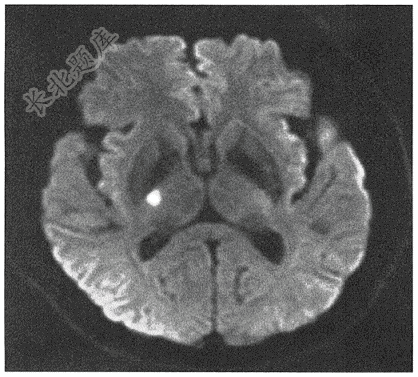

- 单项选择题男,60岁。头晕伴左侧肢体无力2天,头颅MR弥散成像如图( )

A、右侧脑挫伤

B、右侧脑出血

C、蛛网膜下腔出血

D、右侧脑梗死

E、右侧脑膜瘤